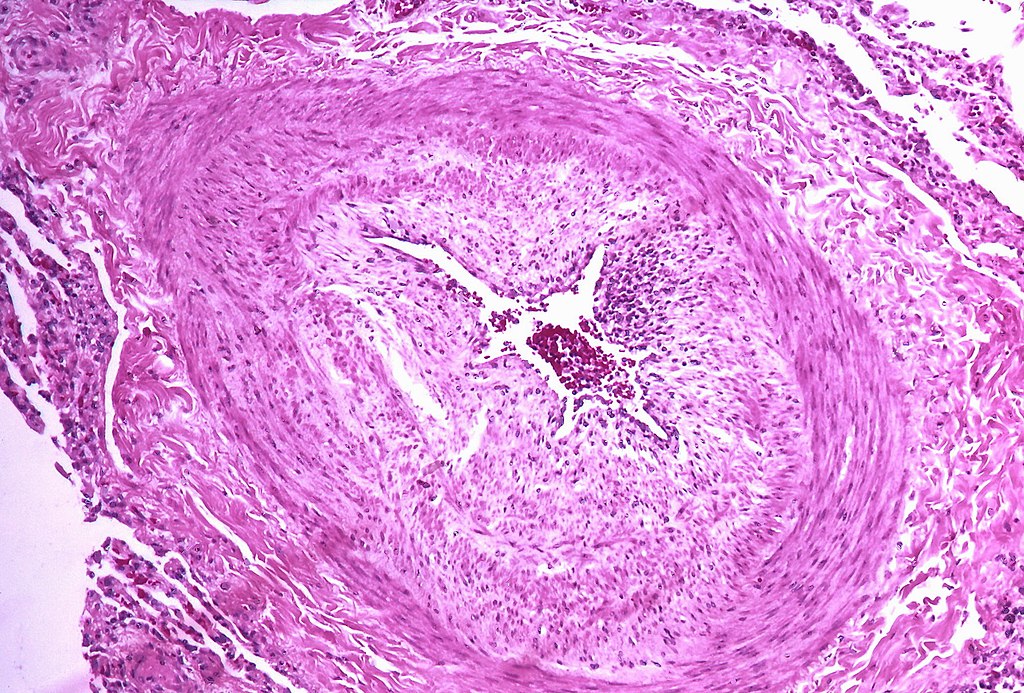

Pulmonary hypertension condition is characterized by atherosclerosis of the pulmonary trunk, smooth muscle hypertrophy of pulmonary arteries, and intimal fibrosis.

Plexiform lesions are seen with severe, long-standing pulmonary hypertension.